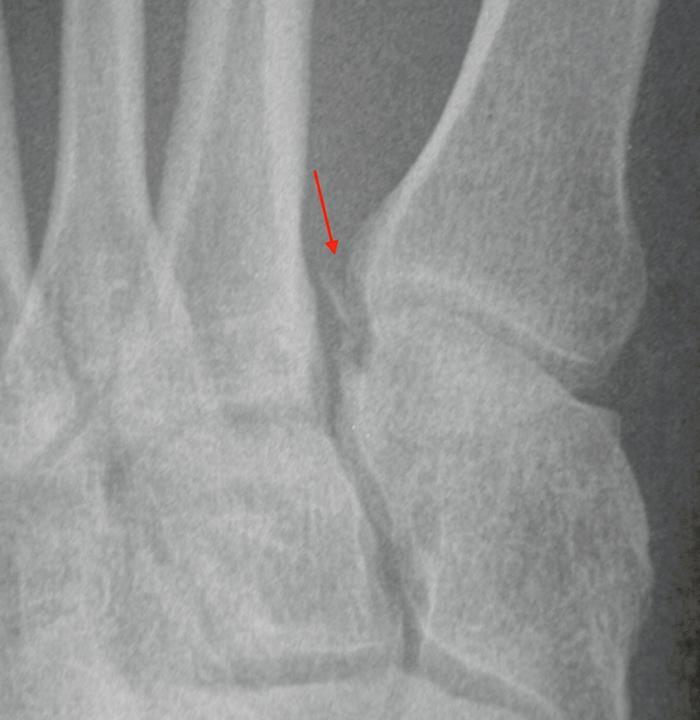

The weight-bearing acts as a stress which can reveal an occult Lisfranc injury. On a normal weight-bearing X-ray the medial border of the 2nd metatarsal lines up with the medial border of the intermediate cuneiform. The base of the 2nd metatarsal is recessed between the medial cuneiform and 3rd metatarsal. It is held in place by three oblique ligaments between the medial cuneiform and 2nd metatarsal. The central interosseous Lisfranc ligament is the strongest, followed by the plantar ligament and the weaker dorsal ligament. There is no intermetatarsal ligament between the 1st and 2nd metatarsals. A normal DP X-ray shows alignment of medial border of the 2nd metatarsal with the medial border of the intermediate cuneiform. A normal oblique X-ray shows alignment of the medial border of the 4th metatarsal with the medial border of the cuboid. If either of these views shows subluxation of the metatarsal base, usually laterally, that indicates a Lisfranc injury (Figure 2). The key is usually the alignment of the base of the 2nd metatarsal and other indicators can be a fleck sign between the base of the 1st and 2nd metatarsal, indicating a bony avulsion (Figure 3), and diastasis between the 1st and 2nd metatarsal, the M1-M2 gap, of >2mm.

Fig 2.jpg

Figure 2: 2nd metatarsal base is subluxed laterally.

Fig 3.jpg 1

Figure 3: Fleck sign.

However, one needs to be aware that the 1st metatarsal base can be unstable and have drifted laterally. If the diagnosis is not certain then additional investigations can include MRI, CT scan and stress views under anaesthetic. An unstable Lisfranc injury requires stabilisation to restore the normal anatomy as incongruity is associated with a poor result. If a diagnosis of a midfoot sprain is made, that is a Lisfranc injury until proven otherwise. The literature is not definitive on how late you can reduce and stabilise a Lisfranc injury, but you can probably do this up to six weeks. If degenerative changes are already apparent, you are probably better to fuse the joints.